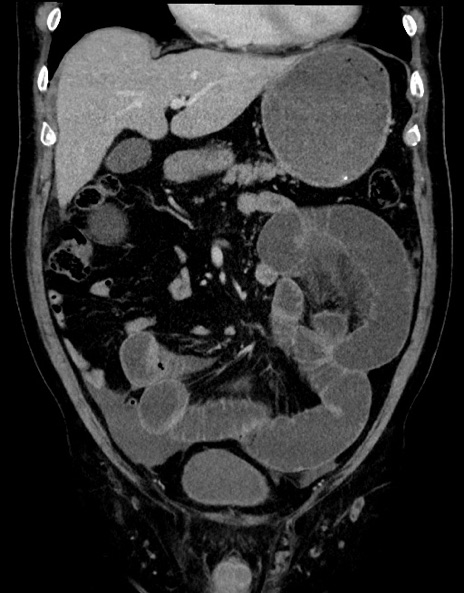

症例15(冠状断像)

【症例】70歳代男性

【主訴】腹痛

【現病歴】今朝から腹痛あり。全体的に痛い。特に左上の方。排ガスが今日はない。冷や汗が出る。

【既往歴】直腸癌術後

【身体所見】左側腹部〜上腹部に圧痛あり。腹膜刺激症状明らかなではない。軽度反跳痛。左下腹部に術後瘢痕あり。

【データ】WBC 7700、CRP 0.02